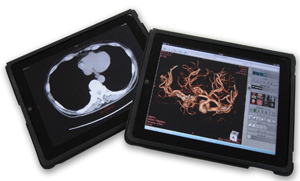

図6 CT大腸解析

メーカーを問わずDICOMサーバに保存されているデータを指定して開くことのできるziostation2は,既存システムとの連携も容易です(DICOM Direct Access)。最新バージョンより,Webブラウザから3D画像処理や閲覧ができる「VersaWeb」でもDICOM Direct Accessがサポートされ,より柔軟性のあるシステム構築が可能になりました。クライアントには汎用PCのほか,iPadでの閲覧もサポートされました(図7)。ワークステーション並みの高度な画像処理を行う「VGR」とiPhoneやiPadでの医用画像の閲覧を可能にする「ziostation2 zioMobile Gateway」と組み合わせることで,院内外を問わず,さまざまな場所から画像診断を行える画像配信ネットワーク構築を実現するソリューションを提案します。